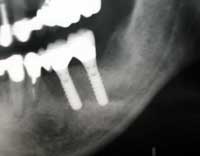

| 術前 | ソケットリフト手術 | 術後2年歯根周囲骨造成良好 |